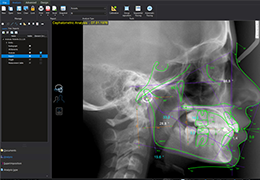

View X-Ray CT & MRI Scans Fast and Easily

Designed for surgeons, Pro Surgical 3D makes it easy to view patient scans quickly. Pro Surgical 3D facilitates the optimal 3D treatment and assessment workflows based on X-ray CT and MRI scans – and best of all, it’s FREE!

Traditional multi-planar slicing

Multi-planar slicing.

Window/level (brightness and contrast) presets.